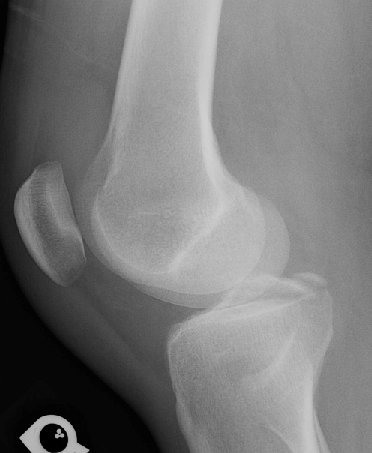

Return to Tibial Spine Fracture